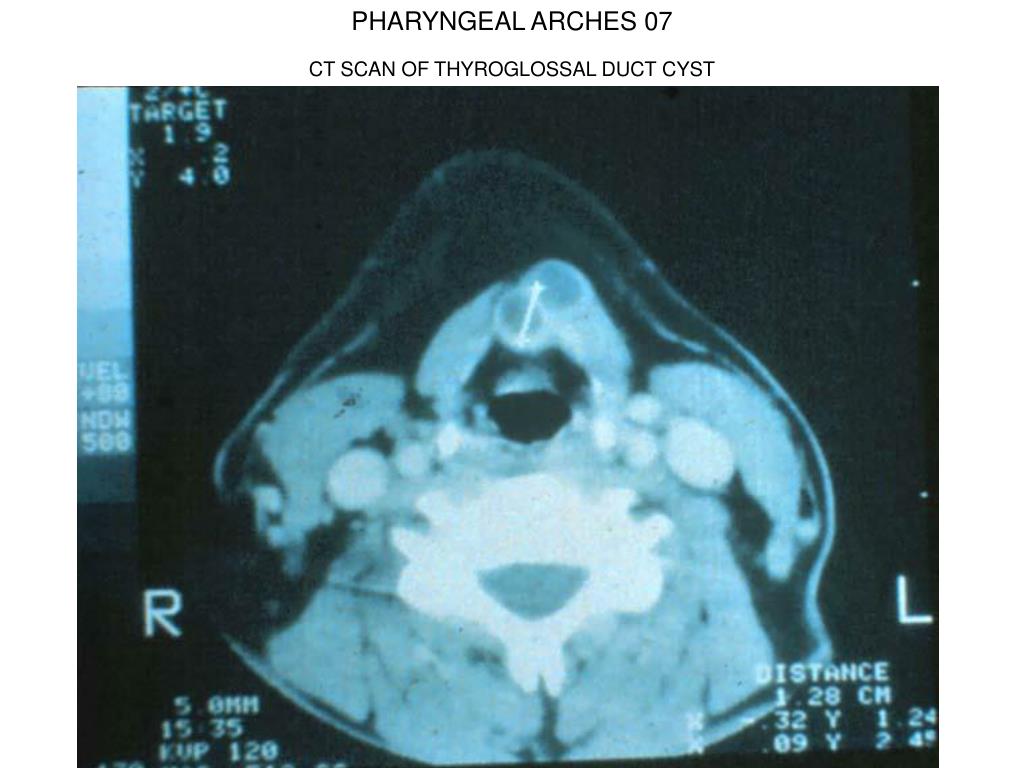

7. PHARYNGEAL ARCHES 07 CT SCAN OF THYROGLOSSAL DUCT CYST